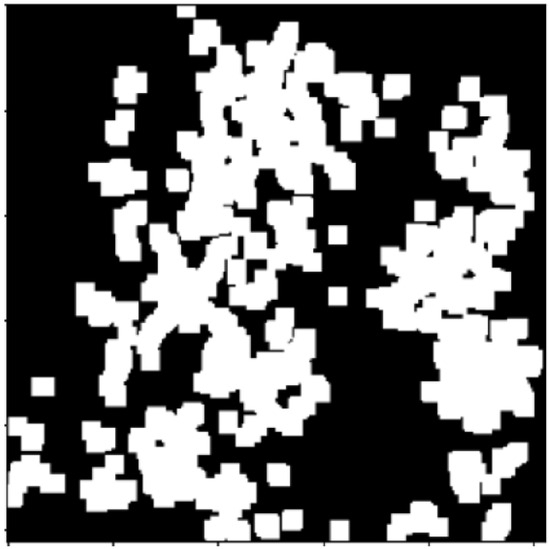

2.2.1. Thresholding

2.2.2. Morphology Operations